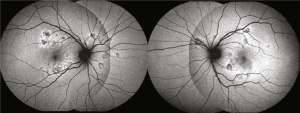

Fundus autofluorescence: hypoautofluroescent lesions with edges that are hyperautofluorescence(Copyright © 2020 Mariana A. Oliveira et al. Reproduced without modifications from an open access article, Management of Acute Posterior Multifocal Placoid Pigment Epitheliopathy (APMPPE): Insights from Multimodal Imaging with OCTA, distributed under the Creative Commons Attribution License)

- Fundus autofluorescence (FAF): Placoid lesions generally appear hypoautofluorescent and may have edges that are hyperoautofluorescent. Hypoautofluorescence may persist at borders after lesion resolution.[6]